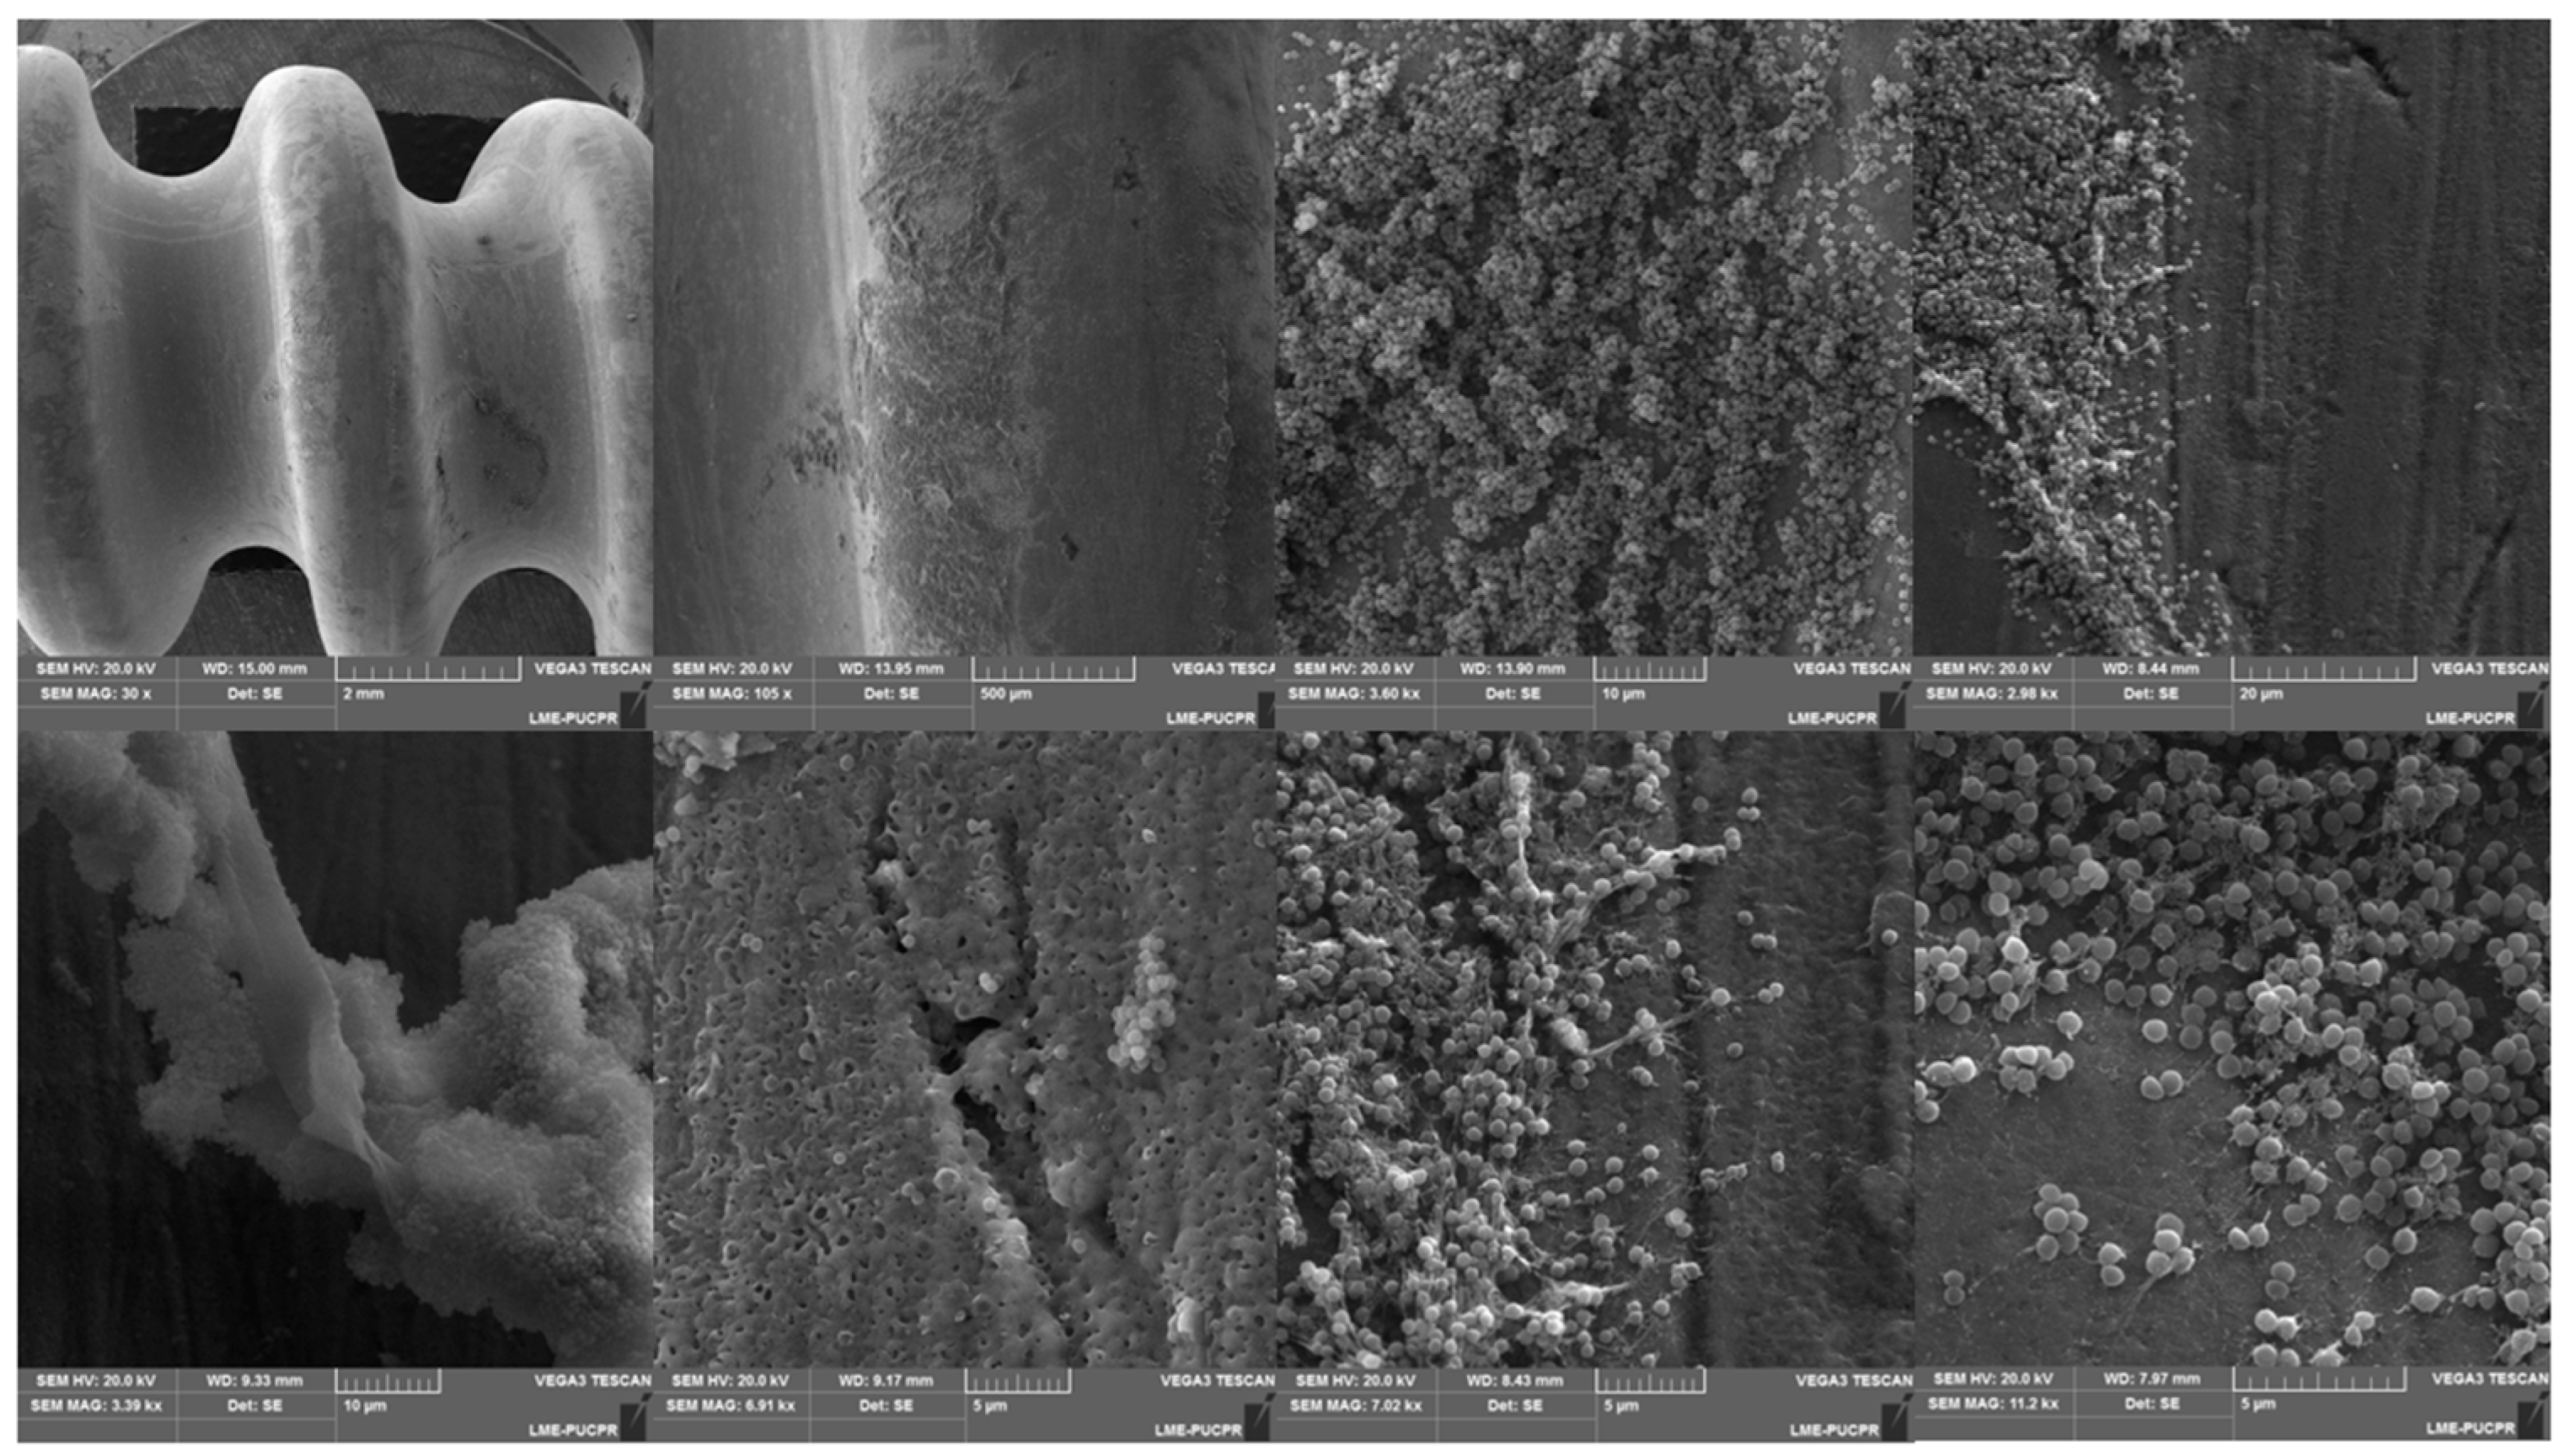

- da Rocha, L.G.D.O.; Ribeiro, V.S.T.; de Andrade, A.P.; Gonçalves, G.A.; Kraft, L.; Cieslinski, J.; Hansen Suss, P.; Tuon, F.F. Evaluation of Staphylococcus aureus and Candida albicans biofilms adherence to PEEK and titanium-alloy prosthetic spine devices. Eur. J. Orthop. Surg. Traumatol. 2022, 32, 981–989. [Google Scholar] [CrossRef] [PubMed]